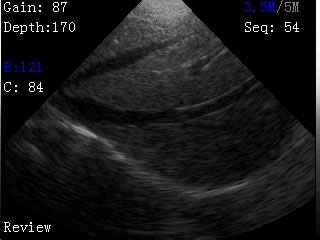

我司最新推出的V2型腕式B超,主机重量仅140克,看成目前全世界最轻的B超。

V2型腕式扇扫B超由主机、探头、外置电池、手握式键盘组成,重量只有140g(不含探头和电池)堪称全世界最轻的B超。

-扫描方式:机械扇扫

-探头频率:3.5MHz/5MHz双频率可变频探头

-扫描深度:≥180mm,70、110、130、150、192mm五档可调

-显示模式:B